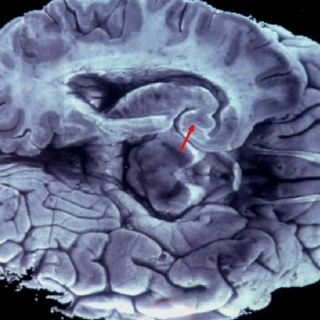

Durante el trabajo, publicado en la revista The Journal of Cell Biology, los científicos analizaron en roedores neuronas del hipocampo, la región del cerebro asociada con los aspectos cognitivos.